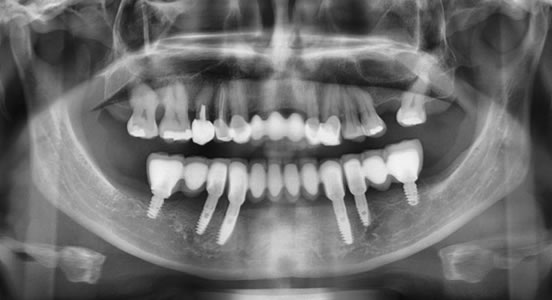

Los antiguos rellenos de oro y plata pueden ser hoy en día cambiados por cerámicas, resinas, cerómeros, ionomeros de resina, vidrio, coronas de substrato zirconia, coronas de cerámica sin metal y de porcelana convencional. Cada uno de ellos tiene sus aplicaciones e indicaciones ajustadas a factores como tamaño de la restauración, existencia o no de tratamientos de canales, hábitos como apretamiento, bruxismo o hábitos parafuncionales. Cual es la mejor opción en cada persona se evalúa en relación a expectativas, presupuesto y posición en la arcada dentaria.

Nuestra capacidad de fabricar dientes practicamente indetectables o diferenciables de los naturales ha avanzado de forma espectacular y predecible. Nuestra mision consiste en imitar la dentadura existente al reemplazar lo que se haya perdido o en desarrollar un esquema idealizado para la sonrisa que el paciente siempre anheló.

Poder restaurar el arco superior con puentes que no cubran el cielo de la boca, recobrar el gusto en la lengua y paladar, simplificar la limpieza y mantenimiento de dientes soportados con implantes, nos abre horizontes jamás sospechados. La gama de sobredentaduras para pacientes que no sean candidatos a puentes fijos, que puedan ser sujetadas a implantes para su estabilidad y retencion es impresionante.